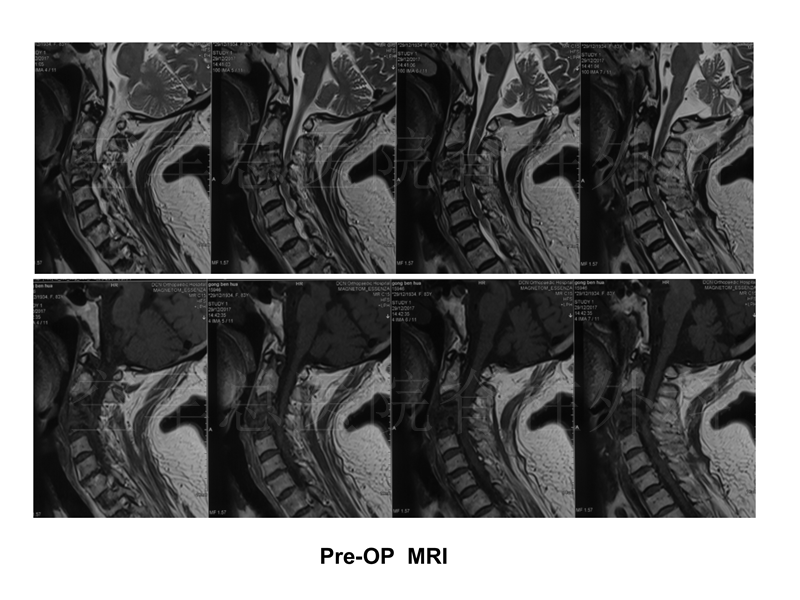

影像检查:

现病史:颈肩部疼痛7月,双上肢麻木2月,四肢无力,大小便障碍1月,无发热、盗汗、乏力等症状

既往史:高血压50年,房颤10余年,房颤射频消融术后6年,脑梗30年,后遗右下肢活动障碍;否认结核、牛羊等接触病史

查体:颈3-4棘突压痛(+);双上肢、胸2以下、双下肢、会阴区感觉减退,右侧为著;双上肢肌力0-I级,双下肢肌力II-III级;双上肢腱反射活跃,双下肢腱反射减弱;Hoffmann(-),巴氏征(+),髌、踝阵挛(-);JOA评分1分。

实验室检查:WBC:4.9G/L,中性粒细胞:76%;C反应蛋白:24.6mg/L、血沉:45mm;结核杆菌γ干扰素释放试验(+);降钙素原(-);布氏杆菌凝集试验(-);肿瘤全套(-);D二聚体:3420;EF:52%;左室壁节段性运动异常;双下肢动脉硬化伴斑块形成;左侧胸膜局限性增厚、粘连,小气道功能下降。